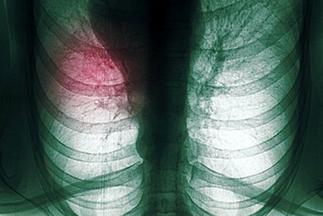

肺癌是我国男性发病率和死亡率最高的恶性肿瘤,并且肺癌的发病率还在持续上升。肺癌治疗目前主要有手术、药物化疗(包括靶向治疗)、放射治疗、免疫治疗、局部姑息治疗和中医药治疗等种类繁多,患者在就医时经常一头雾水,难免有病乱投医,而另一方面医生由于对肺癌疾病的认知不足也可能在一定程度上造成肺癌治疗的延误。为了尽可能延长患者的生命、改善生活治疗,应当把当前最新的、已被证实的最有效的治疗方法结合起来,在确定每个肺癌患者主要的治疗方向后,再为每个患者量身定制具体方法,使每位肺癌患者都得到最佳治疗,所以肺癌治疗规范化下的个体化治疗具有非常重要的意义。

由于肺癌缺乏早期症状及我国总体医疗水平相对落后,目前在我国超过半数的肺癌患者就诊时已经发生远隔转移,失去手术的机会,尽管手术治疗在肺癌所有治疗方法里是最好的,但手术后病人其总体的5年生存率仅在40-50%,手术并不能解决所有的问题。目前肺癌医治是强调以手术为主的综合治疗,有手术条件的患者往往还要在术后补充化疗甚至放疗,或在术前化、放疗后再手术,对于没有手术条件或术后肿瘤复发的病人就要以化、放疗为主,并结合免疫、中医及各种局部减症的治疗手段。